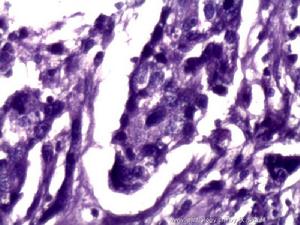

2.組織病理學檢查 術前應儘可能用其他方法作出診斷,如有必要,可行剖腹探查或腹腔鏡手術取活組織病理學檢查。